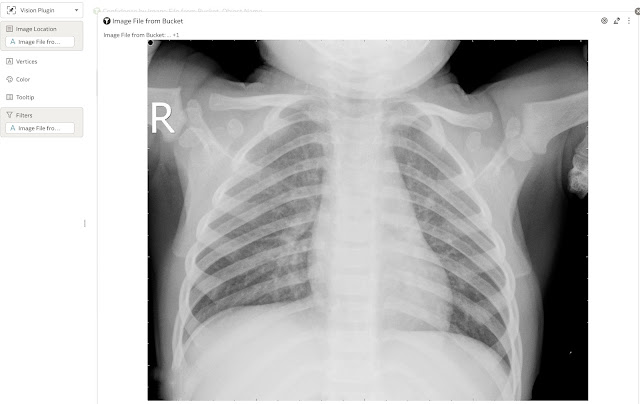

The left part of the visualisation is a simple pivot table containing image name and location and confidence for Pneumonia or Normal lungs.

However for the right part Vision Series plug-in is used. Let’s take a look at it.

Visualisation's parameters for our example are rather simple. We are showing only one image at the time, and Image File from Bucket is located in Image Location field. If we were using this visualisation component for object detection, then object coordinates would be put into Vertices field.

As image is displayed one by one (always is displayed the 1st from the list), the pivot table visualisation is used as a filter.